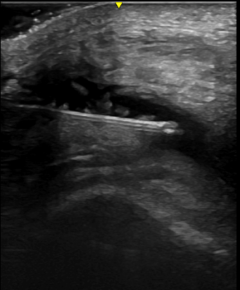

Ultrasound used to accurately guide needle placement into a joint effusion

Ultrasound used to accurately guide needle placement into a joint effusion.

Injections have historically been performed using touch to identify physical landmarks, without the ability to confirm the accuracy of the injection. Ultrasound can be used to help providers improve the accuracy and effectiveness of injections.

During an ultrasound-guided injection, the needle can be visualized in “real time,” and adjustments can be made if needed.  Ultrasound guided injections have been shown to reduce injury, have less side effects, and improve patient comfort. Both steroids and hyaluronic acid injections can be done under ultrasound guidance.